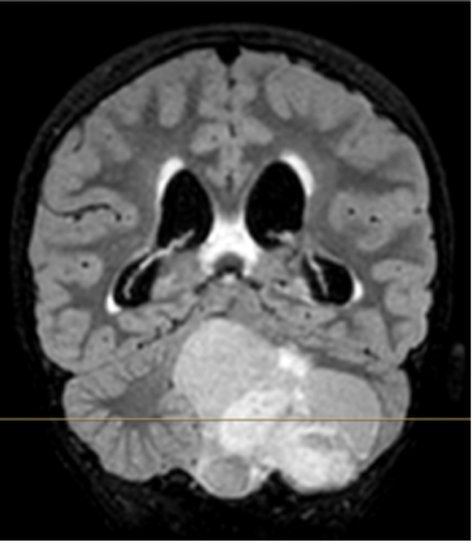

Infine, nei giorni successivi, il ragazzo si sottopone alla RM encefalo che documenta una voluminosa lesione espansiva in fossa cranica posteriore a partenza cerebellare sinistra con componente solida e cistica, idrocefalo triventricolare con segni di trasudazione ependimale (Figura).